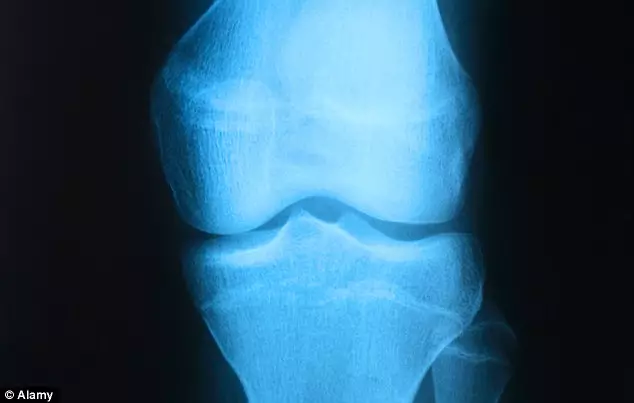

牙買加盛產田徑選手,無論是運動訓練專家還是科學家開始探尋保特等飛人成功的秘訣。有研究人員發現,牙買加不斷湧現天才短跑選手的原因在於他們都擁有完美對稱的膝蓋。

英國《每日郵報》報道,羅格斯大學的人類學與生物進化學教授Robert L.Trivers和他的團隊一直在研究膝蓋極佳的對稱性與短跑的開係。研究人員測量了74位牙買加短跑精英選手後,與116名相同年齡的非短跑選手的牙買加人進行對比。他們發現,短跑運動員膝蓋比普通人更對稱,其中膝蓋更對稱的30名短跑選手都是100米跑手,因為他們毋須跑彎道,膝蓋也更加對稱。

圖片來源:Alamy

Robert指,這是第一次有人透過科學研究發現膝蓋對稱性對於短跑運動員在衝刺速度中存在變量關係:「對稱性越高的人往往更健康、更好看,而且對稱性越高也令移動更加容易,步幅更高效,更節省能量。」